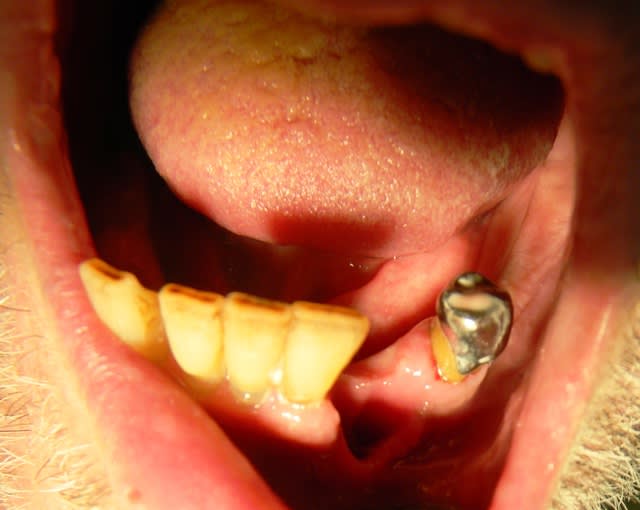

22/11/2010 à 17h14

-vous vous êtes brossé les dents avant de venir ?

-ah oui! pendant 3 minutes

(au moins...! et réparti sur 3 semaines)

la prothèse sup , c'est moi qui l'ai nettoyé. imaginez comment elle devait être!